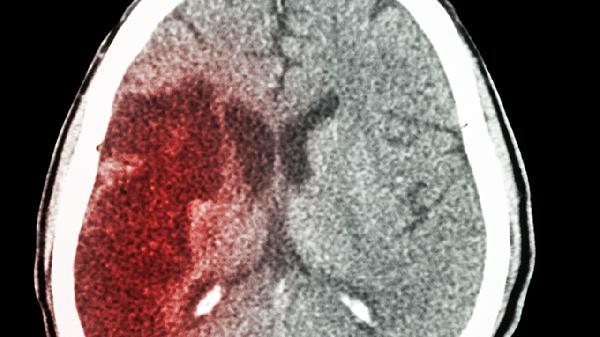

产伤或早产儿脑室内出血后,血块机化可造成中脑导水管或基底池粘连。此类继发性脑积水多在出生后2-3周显现,需通过神经内镜进行粘连松解,严重者需放置可调压分流管。